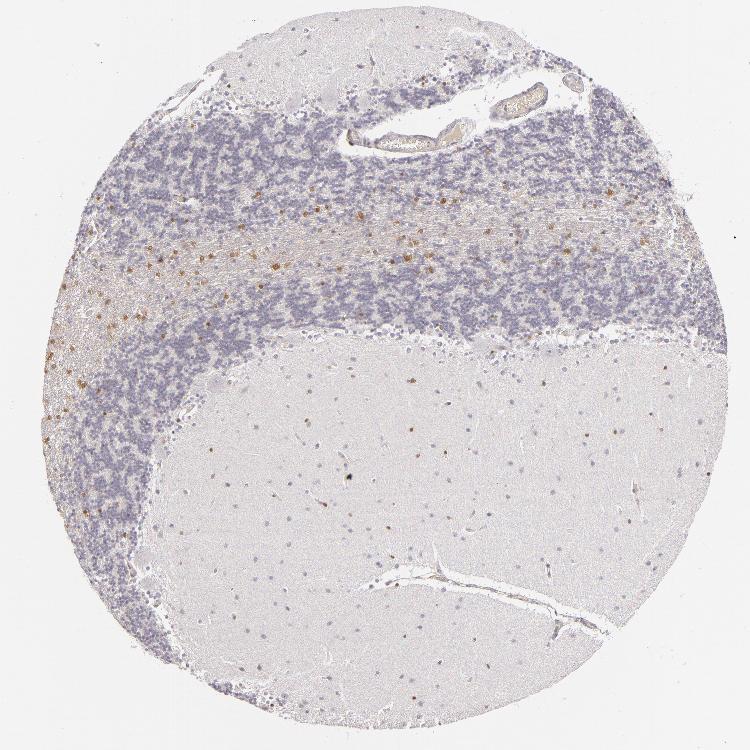

CEREBELLUM - Antibody stainingi

Antibody staining in the annotated cell types in the current human tissue is reported as not detected, low, medium, or high, based on conventional immunohistochemistry profiling in selected tissues. This score is based on the combination of the staining intensity and fraction of stained cells.

Each image is clickable and will lead to virtual microscopy that enables deeper exploration of all samples and also displays staining intensity scores, fraction scores and subcellular localization as well as patient and tissue information for each sample.

Antibody HPA001581

Purkinje cells Not detected

Cells in granular layer Medium

Cells in molecular layer Not detected